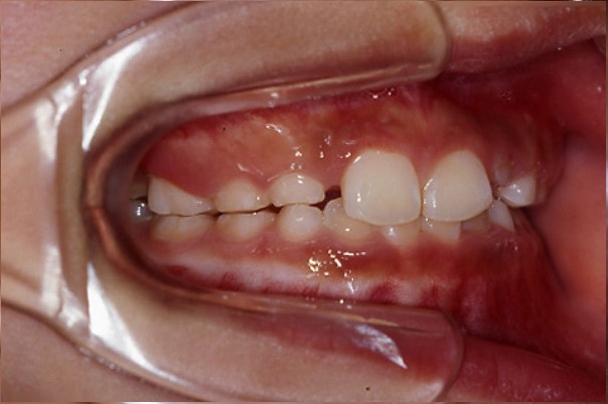

「上顎前方牽引装置」という装置を使用することになりました。この装置は上の歯にセメントで固定する「口腔内装置」と、つけ外し可能な「フェイスマスク」から構成されます。この装置には上あごを前方に成長させる効果があり、骨格的な受け口にアプローチ可能なものです。この装置の有効期間には限りがあり、小学校4~5年生頃にはあまり効かなくなってしまいます。この患者さんは早期に来院してもらえたため効果が期待できると考え、急いで治療を開始しました。フェイスマスクは睡眠時のみ使用しました。フェイスマスクのつけ外しは、最初の数日はお母様に手伝ってもらっていましたが、1か月すれば自分で鏡なしでも着脱できるようになっていました。装置使用による痛みはほとんどなかったとのことです。

徐々に上あごが前方に成長し、使用開始5か月で受け口がきれいに治りました。その後も装置の使用を継続し、ちょうど1年で装置を撤去しました。現在は上下のあごの状態や歯並びに全く問題がない状態ですが、身長が伸びている間は下あごが成長してくるため、13歳頃まで下あごの成長に留意しながら経過観察していく予定です。